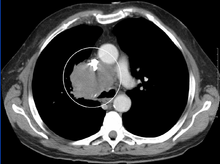

The main techniques of diagnosing SVCS are with chest X-rays (CXR), CT scans, transbronchial needle aspiration at bronchoscopy and mediastinoscopy.[3] CXRs provide the ability to show mediastinal widening and may show the presenting primary cause of SVCS.[3] CT scans should be contrast enhanced and be taken on the neck, chest, lower abdomen and pelvis.[3] They may also show the underlying cause and the extent to which the disease has progressed.[3]